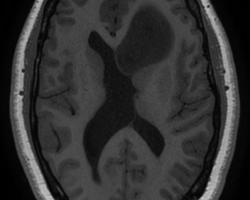

- IRM : coupes axiales, séquences en diffusion B1000, perfusion, T1 et T2 : tumeur hypoT1, hyperT2, peu de diffusion = peu d’œdème, localisation plutôt frontale. Pas de prise de contraste (pas de cliché ici = à compléter) Compte tenu de l’âge, évocateur d’un gliome bas grade. De ce fait, rechercher une comitialité avant tout geste chirurgical.

IRM : lésion basifrontale gauche développée aux dépens du gyrus rectus qui remonte vers l’hypothalamus comprimant les foramens de Monro induisant une probable hydrocéphalie obstructive. Pas de prise de contraste mais séquences en perfusion non exploitables.